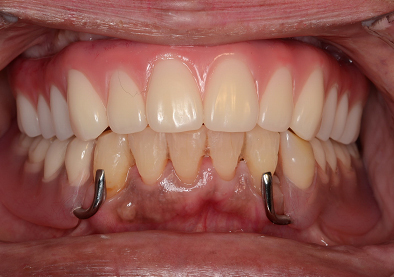

下顎のALL-ON-4①(下の歯のオールオンフォー)

-

- 主訴

- もともと入っているインプラントの周りが腫れ、残りの歯も動いているので力が入らない

- 治療内容

- 下顎右側に以前埋入したインプラントの撤去を行い、歯周病の進行が著しかった残存歯の抜歯を行うと同時にインプラントの埋入を行い、当日仮歯を装着した

- 治療費用

- 下顎ALL-ON-4:4,000,000円(税別)

- 治療期間

- 6ヶ月